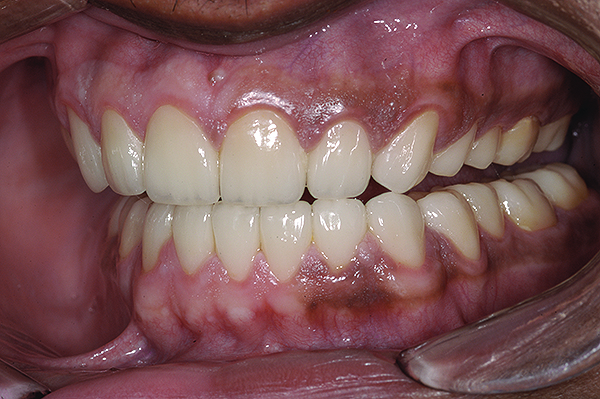

The final restorations depicted restoration of form, function, and beauty, with good harmony of restoration and the periodontium (Figure 19 through Figure 25). MIP was in harmony with CR, and right and left lateral excursion discluded all posteriors with anterior group function. The postoperative orthopantomogram (OPG) (Figure 26) shows the treatment done while maintaining the vitality of anterior teeth.

Figure 19. Postoperative frontal smile.

Figure 19

Figure 20. Postoperative 1:2 retracted frontal view.

Figure 20

Figure 23. Postoperative 1:1 retracted frontal view.

Figure 23